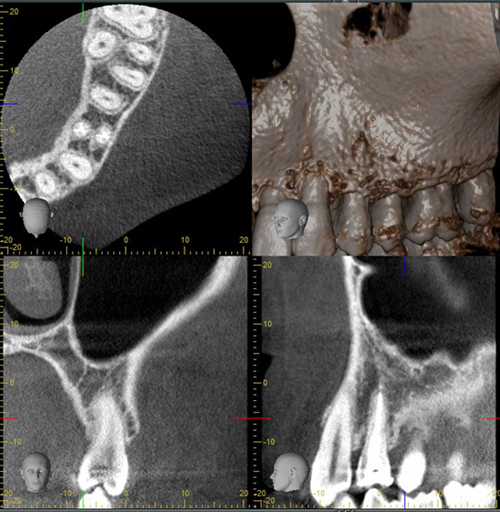

3D տոմոգրաֆիան մեծ նշանակություն ունի իմպլանտոլոգիայում, պարօդոնտոլոգիայում և էնդոդոնտիայում: Այս հետազոտության շնորհիվ բժիշկը կարող է տեսնել ստոմատոլոգիական բնույթի մի շարք խնդիրներ, ինպես նաև տվյալ պացիենտին բնորոշ անատոմիական առանձնահատկությունները. ատամի կառուցվածքը, ոսկրային հյուսվածքը, հայմորյան ծոցերը և այլն:

Թերապևտ-ստոմատոլոգի համար, նախքան բուժում սկսելը, շատ կարևոր է իմանալ, թե տվյալ պացիենտի մոտ քանի արմատախողովակից է կազմված ատամը, որպեսզի անհրաժեշտության դեպքում կատարի ճիշտ մշակում և հերմետիկ փակում: Ոսկրային հյուսվածքի ծավալի և կազմի մասին 3D տոմոգրաֆիայի օգնությամբ ստացած տեղեկատվությունը ատամների իմպլանտացիայի ժամանակ բժիշկին հնարավորություն է ընձեռում իմպլանտը ճիշտ տեղադրել: